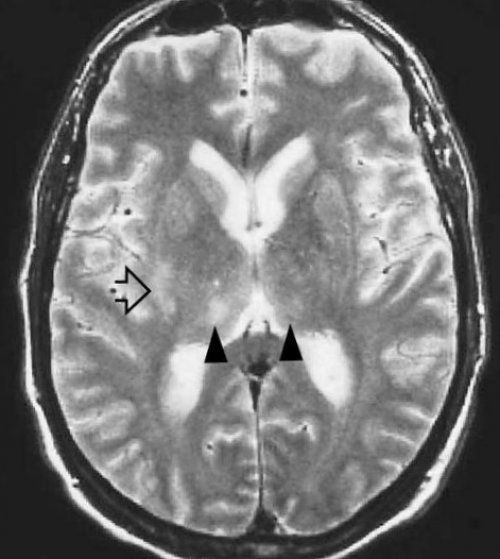

МРТ головного мозгас частичным сохранением